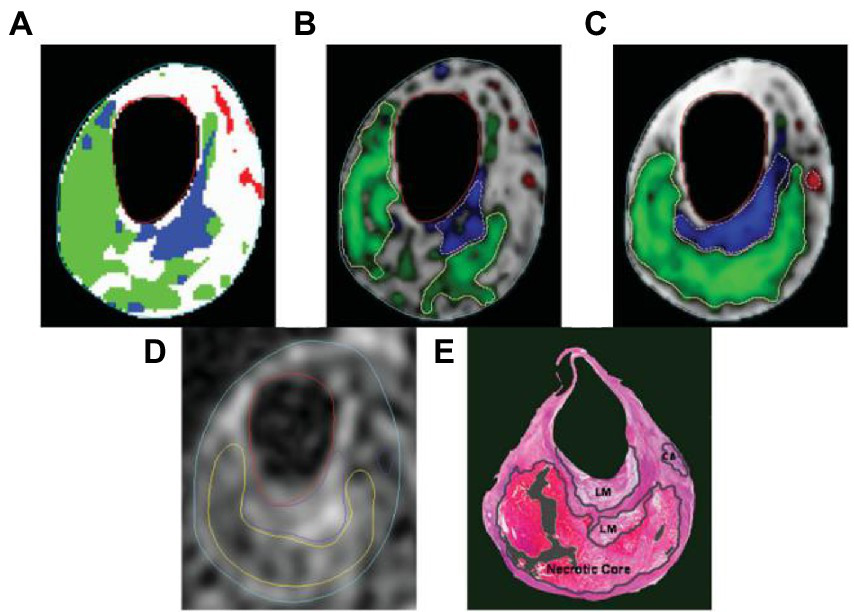

Table 4 lists the classification accuracies in terms of sensitivity and specificity for each pixel in the testing set. Both blinded manual and automated segmentation yield similar results, showing high specificities for all tissue categories and great sensitivity for fibrous tissue. In contrast to the loose matrix, which has very poor sensitivity, necrotic core and calcifications sensitivity is good. This metric is pessimistic for small locations, like the majority of calcifications and confusion matrix, which can mainly cause a slightly lower sensitivity. The segmentation result in Figure 6 serves as an illustration of this observation.

Figure 6

The following segmentation results are displayed on a T2-weighted image. (A) Automatic labeling result by Gaussian classifier. (B) Probability map and region contours based only on intensity, with a necrotic core in green, calcification in a red, loose matrix in blue, and fibrous tissue in gray. (C) Corresponding results with morphologic information. (D) Manual segmentation result. (E) Corresponding histology specimen used to direct contour placement in (D) dark areas.